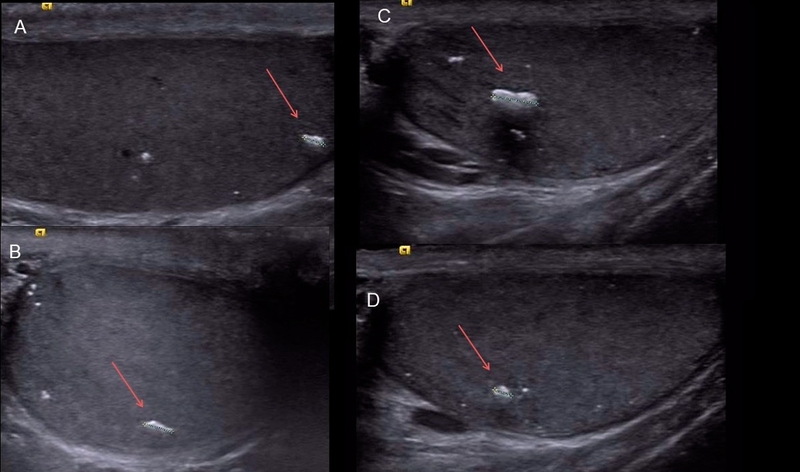

Vôi hóa tinh hoàn là tình trạng lắng đọng canxi bất thường trong mô tinh hoàn, tạo thành những nốt nhỏ có thể phát hiện qua siêu âm. Đây không phải là bệnh lý riêng biệt nhưng nó có thể liên quan đến viêm nhiễm, chấn thương hoặc rối loạn chuyển hóa. Trong hầu hết các trường hợp, vôi hóa tinh hoàn không gây nguy hiểm. Tuy nhiên, nếu đi kèm với các bệnh lý nền, nó có thể ảnh hưởng đến chức năng sinh sản và sức khỏe nam giới.

Để chẩn đoán vôi hóa tinh hoàn, bác sĩ sẽ chỉ định siêu âm tinh hoàn để phát hiện các nốt vôi hóa, xét nghiệm máu để kiểm tra dấu hiệu viêm nhiễm, xét nghiệm nội tiết tố nam (FSH, LH, Testosterone) để đánh giá chức năng sinh tinh và sự cân bằng hormone. Trong một số trường hợp, xét nghiệm máu cũng giúp tầm soát ung thư tinh hoàn bằng các chỉ số AFP, hCG và LDH. Nếu vôi hóa tinh hoàn ảnh hưởng đến chức năng sinh tinh, bác sĩ sẽ chỉ định thực hiện tinh dịch đồ.